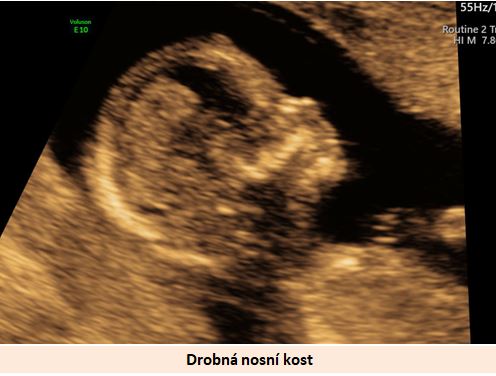

Ultrazvuková diagnostika se při screeningu v 1. trimestru opírá o šířku podkoží v záhlaví plodu, osifikaci nosní kůstky a nálezu abnormálních průtoků v srdci plodu (trikuspidální regurgitace, reversní tok v ductus venosus).

Pracoviště se zkušenostmi v prenatální diagnostice a s dobrým přístrojovým vybavením je schopno vyslovit podezření na tento syndrom ve více jak 90% případů již při ultrazvukovém vyšetření ve 12-13. týdnu těhotenství. .